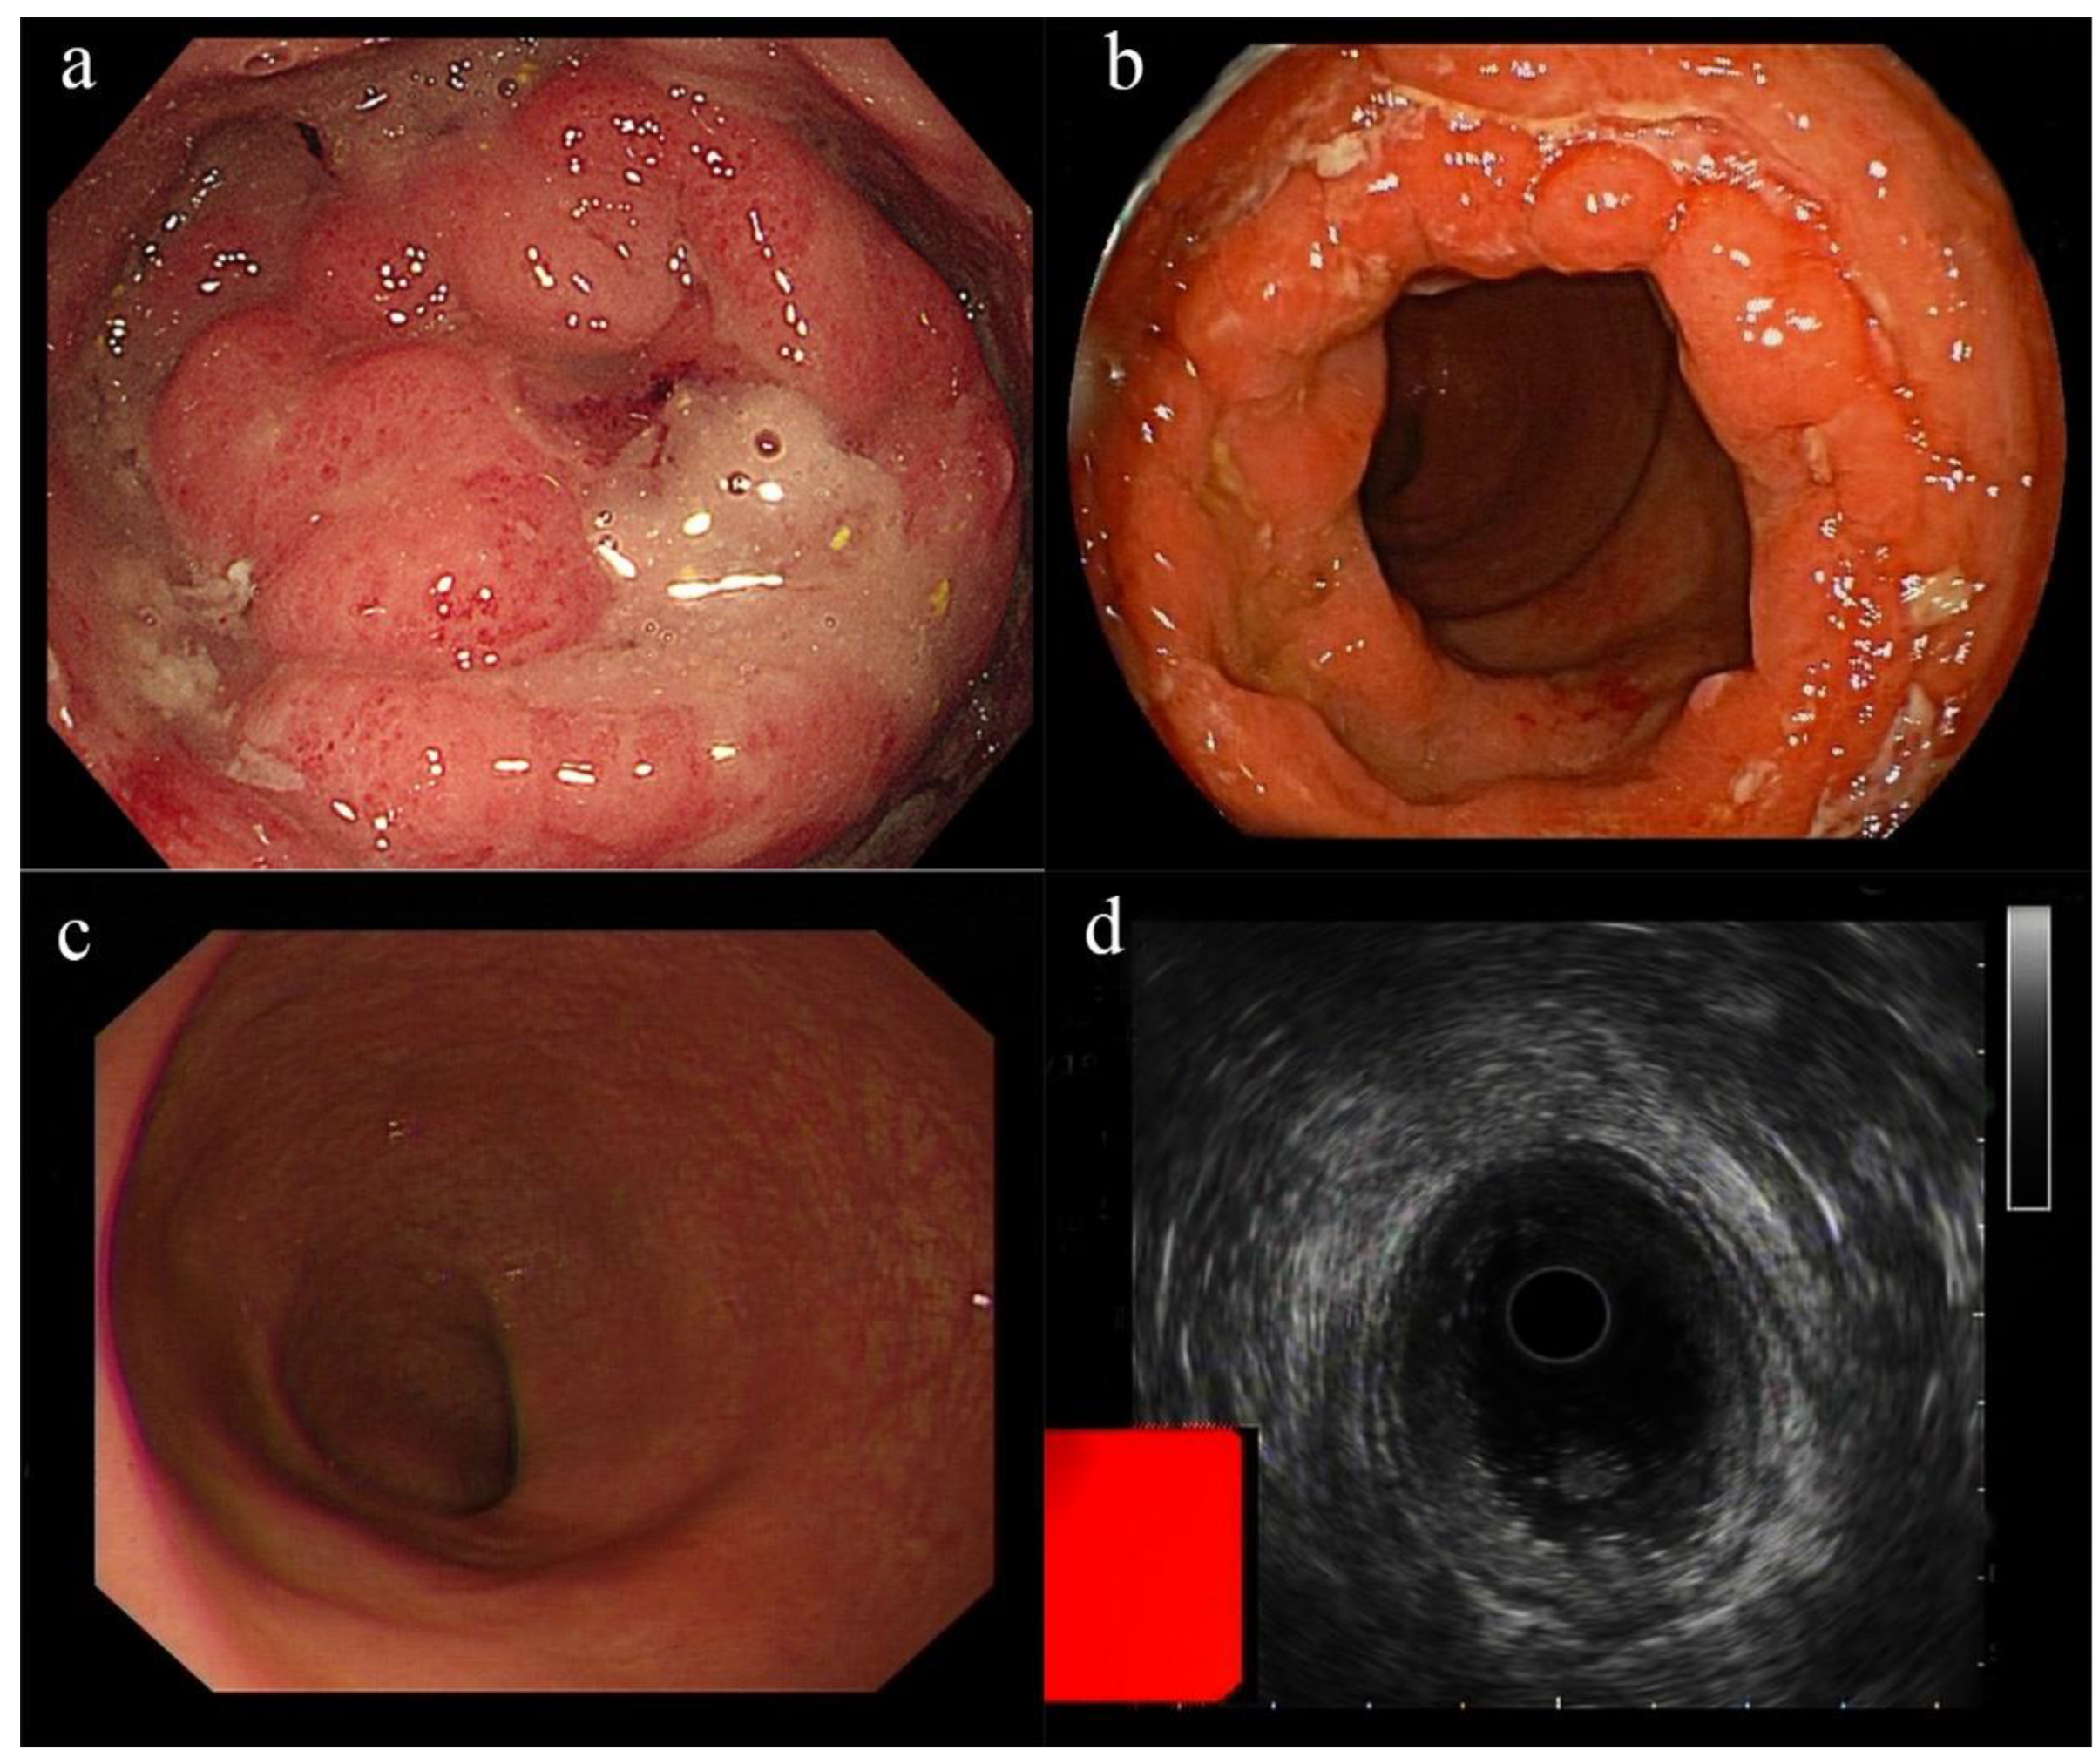

| Our report | A 58-year-old Chinese woman | None | CMV proctitis | Three days after the second dose of CoronaVac COVID-19 vaccine | Constipation, perianal discomfort, and abdominal distention | Proctosigmoidoscopy revealed new circumferential growth at the anorectal junction, with an uneven surface and ulceration. A biopsy revealed moderately active chronic proctitis with CMV infection | The patient received 250 mg of ganciclovir twice daily for 5 days, and oral ganciclovir was continued after discharge | Cure |